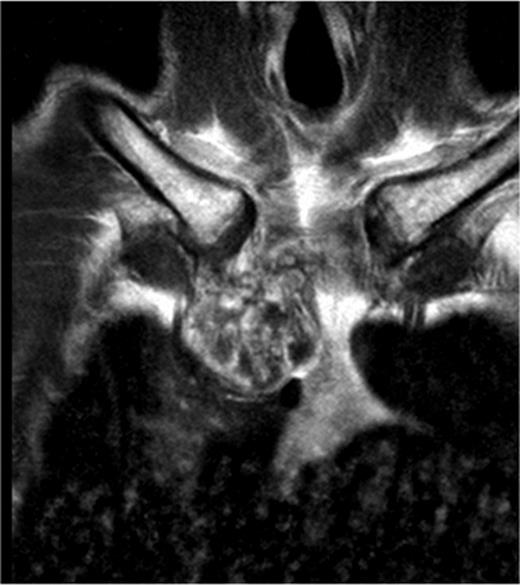

A 60-year-old male patient presented himself to the outpatient clinic of our department with a progressive sternal mass. An MRI scan indicated a tumour involving the manubrium extending to the first and second ribs and involving the right clavicle and sternoclavicular joint (Figs 1 and 2). Based on radiological evaluation, a core biopsy was obtained and a low-grade chondrosarcoma was characterized. Radiological evaluation indicated primary tumour resection to be the treatment of choice. Radical excision of the tumour was performed and resulted in resection of the manubrium, as well as the medial third of the right clavicle and the right first and second ribs. Steel wires through the sternum and left sternoclavicular joint spanned the 6.5 cm sternal defect (Figs 3 and 4) and a polypropylene mesh filled with methyl methacrylate composite (Surgical Simplex®), Howmedica Osteonics, Limerick, Ireland, was placed, yielding a stable reconstruction of the sternal defect (Figs 5–8). The sternocleidomatoideus muscle was re-inserted to the polypropylene mesh. Pathological examination showed complete excision of the tumour. The patient recovered uneventfully and was discharged 7 days post-operatively. At seven year follow-up, the patient displayed excellent functional and aesthetic results. Optimal function of his shoulders allowed a complete return to work and other activities without disabilities.

The axillar slides of the MRI of the patient showing the ingrowth of the tumour in the thoracic cavity in relation to the intrathoracic organs.